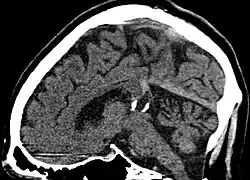

| Calcified cyst of pineal gland in CT. Sagittal MPR. |

A pineal gland cyst is a usually benign (non-malignant) cyst in the pineal gland, a small endocrine gland in the brain. Historically, these fluid-filled bodies appeared on 1-4% of magnetic resonance imaging (MRI) brain scans, but were more frequently diagnosed at death, seen in 4-11% of autopsies.[1] A 2007 study by Pu et al. found a frequency of 23% in brain scans (with a mean diameter of 4.3 mm).[1]